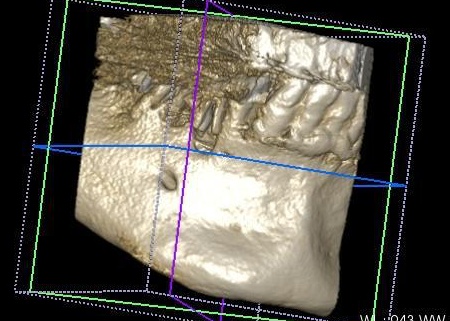

インプラントの埋入設計をしました。